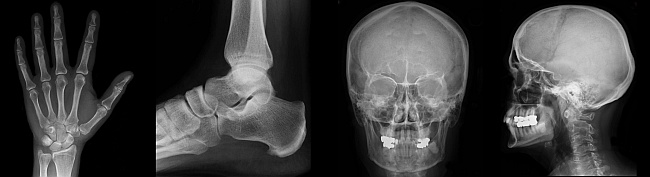

Konventionelles Röntgen (Bucky + Stativ) mit digitalem Foliensystem

• Schädel- und Nasennebenhöhlen(NNH)-Diagnostik

• Knochen- und Gelenkdarstellung

Funktionsweise des digitalen Röntgens

Beim digitalen Röntgen ist immer noch ein Röntgenstrahler notwendig.

Durch die Digitaltechnik kann die Strahlendosis jedoch reduziert werden.

Vorteil der Digitaltechnik ist vor allem der bessere Weichteilkontrast bei gleicher räumlicher Auflösung.

Fehlbelichtungen können durch die digitale Nachbearbeitungsmöglichkeit ausgeglichen werden. Bildwiederholungen können dadurch vermieden werden.